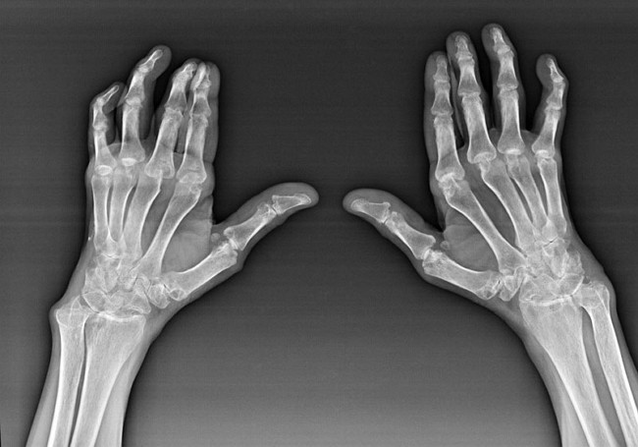

Rheumatoid arthritis

Rheumatoid arthritis is a disease in which human immune system damages the body's tissues.In other words, rheumatoid arthritis is an autoimmune disease.This disease also has a system, because many tissues are affected by it (Muscle, joints, ships, etc.) and agencies (Heart, kidney, lung, etc.) in the body.

Despite the fact that rheumatoid arthritis is a systematic disease, at a greater level, the joints are affected, while the damage of other tissues and organs is in the background.With this disease, almost all types of brush joints can be affected (Wrist, wrist tube, metacarpal-phalanx, joint phalanx).Ordinary injury (Those things.The same joints are affected) On both hands, accompanied by swelling, pain in damaged joints.In the morning, during the lifting process from the bed, there are some hardness in the affected joints, which can last for about 1 hour and then disappear without traces.

Quite often with rheumatoid arthritis near the affected joints of the brush (More often than piano-phalanx, phalanx) The low notes appear.They are a circular team lying under the skin.On the brush, these formations arise most often on the back.When touching, they are dense, not working, no pain.The number of them may change.